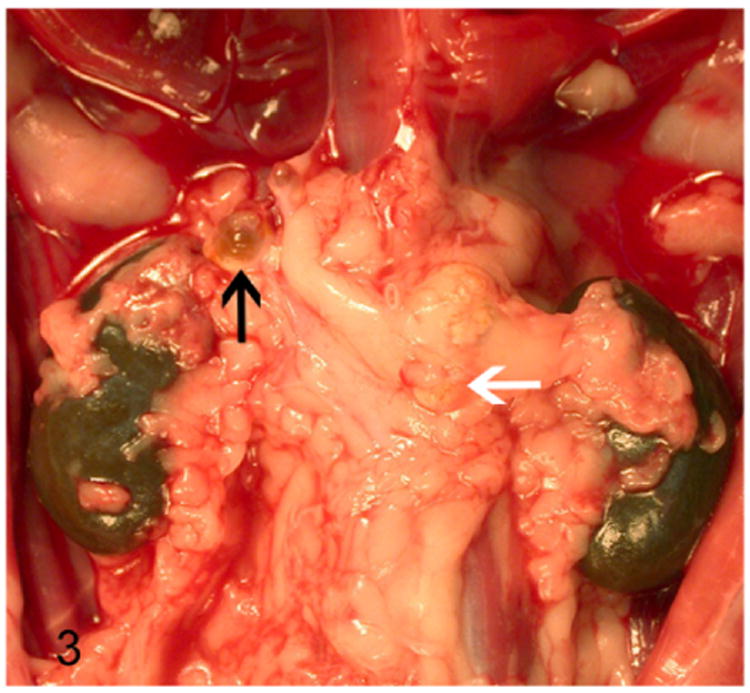

The proliferative lesions in the adrenal cortex of ferrets manifests as hyperplasia, adenoma, and carcinoma. On gross examination, these proliferative lesions reveal nodular or diffuse adrenal gland enlargement, discoloration, cyst formation (Fig. 3), and poor demarcation of the corticomedullary junction. The histological features of adrenocortical hyperplasia and adrenocortical neoplasms are described in Table 3.41

Figure 3.

Proliferative lesions of the adrenal gland, ferret. Adrenocortical tumor. Cystic right adrenal gland (black arrow) and an enlarged neoplastic left adrenal gland (white arrow) embedded within adipose tissue.

Solitary or multiple cysts and tubular structures are occasionally encountered as an incidental finding in normal, hyper-plastic, and neoplastic adrenal glands of ferrets.41,79 These cystic structures often affect the right adrenal gland (Fig. 3) due its close proximity to the caudate liver lobe.79 On gross examination the cysts contain waxy translucent material. Histologically, the cysts are lined by single layer of attenuated low cuboidal epithelium. The cysts contain homogenous eosinophilic material (Fig. 5) occasionally admixed with cellular debris and mineral. The epithelial cells lining the cysts demonstrate strong immunoreactivity to cytokeratin 7, 14, 19, and AE1/AE2, which suggests that the cysts are biliary in origin.79